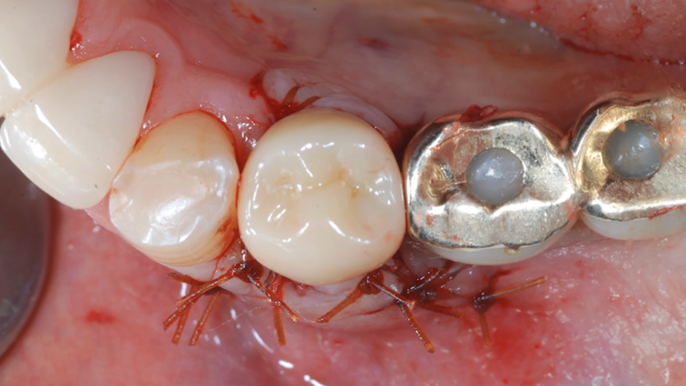

Clinical case: : R2GATE guided surgery & immediate implant placement

- Courtesy of Dr. Kwang Bum Park, Korea -

Keywords

Dr. Kwang Bum Park, immediate loading, digital guided surgery, digital ONE-DAY implant, maxillary anterior, #21, guided surgery, immediate loading, AnyRidge, R2GATE, Mega ISQ, MEG Torq, R2GATE Full Surgical Kit

Products:

implant system, R2GATE Guide, R2GATE full surgical kit, Mega ISQ